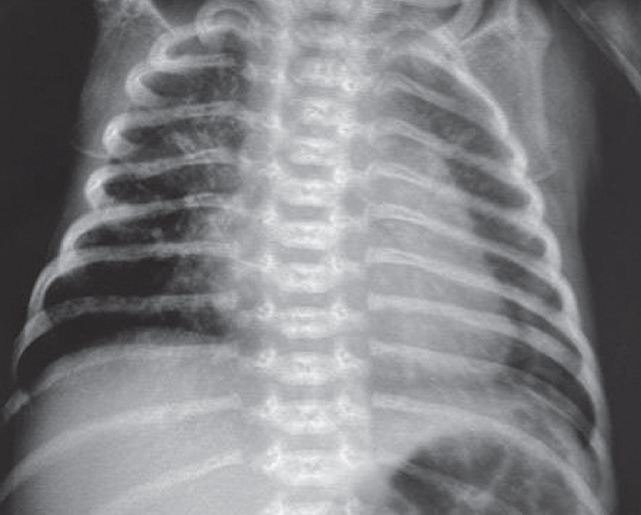

В левый главный бронх повторно введен порактант-альфа. После выполнения манипуляции отмечается клинико-рентгенологическое улучшение (рис. 4) — увеличение SpO2 до 90 %, положительная динамика газового состава крови.

Рис. 4. Рентгенограмма органов грудной клетки новорожденного после повторного монобронхиального введения сурфактанта

Fig. 4. Chest X-ray of newborn after repeated monobronchial administration of surfactant